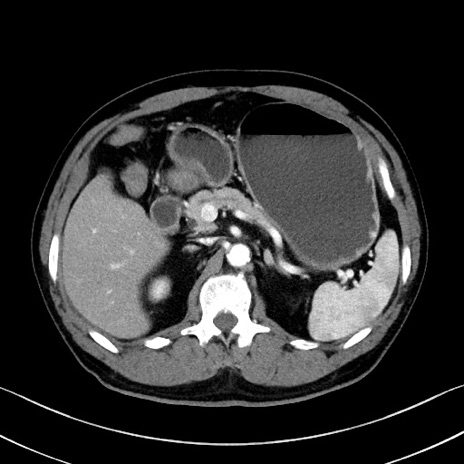

症例35(横断像)

【症例】70歳代 男性

【主訴】腹部膨満、嘔吐

【現病歴】昨日より腹部膨満感出現。本日増悪し、仙痛出現。嘔吐あり、受診。

【既往歴】糖尿病、胆摘後

【身体所見】BP 149/80mmHg、HR 74/min、BT 35.9℃、腹部:膨満、軟、圧痛なし。腸雑音減弱あり。上腹部正中切開瘢痕あり。

【データ】WBC 13500、CRP 1.72